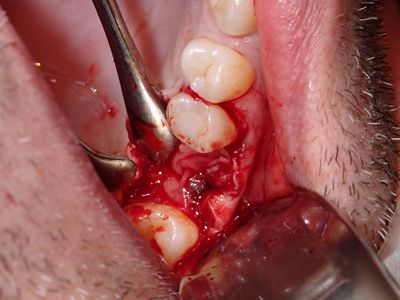

PWong - remove impl 26 and graft

implant placed 4 months ago in 4-5mm height of bone, no sinus lifting procedure, loose, removed implant with forcep, flapped region, large sinus communication, about 6mm+ diameter, likely larger, placed fibrin membrane followed by collagen membrane soaked in prf fluid at floor of sinus, membrane oversized, borders in internal aspect of defect, packed defect with sticky bone from 50/50 allograft, additional collagen membrane and fibrin membrane over crest